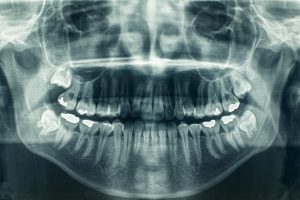

panoramic dental xray

Bone graft procedures are a lot easier than some people think. You will first come in for a consultation and series of x-rays. Next, we will discuss your bone graft options with you and will schedule the procedure. Our highly trained dentist will then make an incision into your jawbone where the bone graft is needed. The bone graft will be placed, and the incision will be closed.